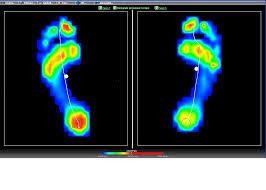

La Baropodometria è una sofisticata metodica di indagine non invasiva che consente di misurare la quantità di carico esercitata su ciascun punto d’appoggio del piede, garantendo misurazioni precise, istantanee e ripetibili.

L'esame Baropodometrico è un test che permette di valutare quindi la qualità dell'appoggio a terra dei piedi e fornisce informazioni sulle pressioni che vengono scambiate tra la superficie di appoggio di questi ed il terreno, inoltre valuta in modo approfondito la modalità di esecuzione del passo ed eventuali alterazioni della deambulazione.

Le misurazioni effettuate sono accompagnate da immagini a colori con analisi dei valori pressori.